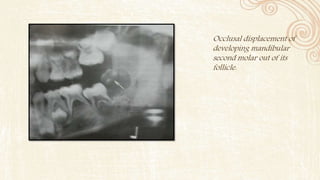

• Developing teeth in their crypts and teeth undergoing eruption may be

displaced in the occlusal direction or into the oral cavity before root

development resulting in the premature loss of teeth

Occlusal displacement of

developing mandibular

second molar out of its

follicle.